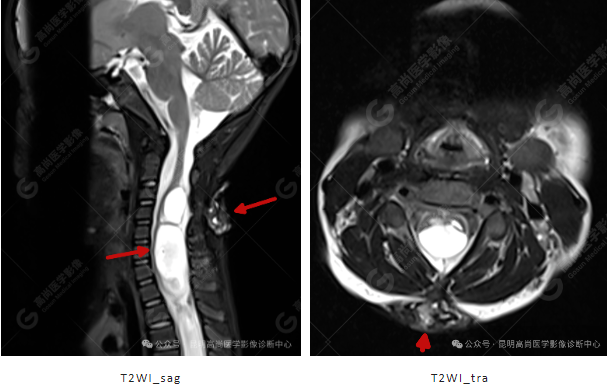

颈 3-5 层面颈后部软组织不规则片状异常信号影,脊膜膨出可能;颈 3、4 棘突局部显示不清;颈胸髓内(约颈 3-胸 9 椎体水平)异常信号影,考虑囊肿并局部颈髓空洞可能,肿瘤或其他待排;请结合临床及相关检查。